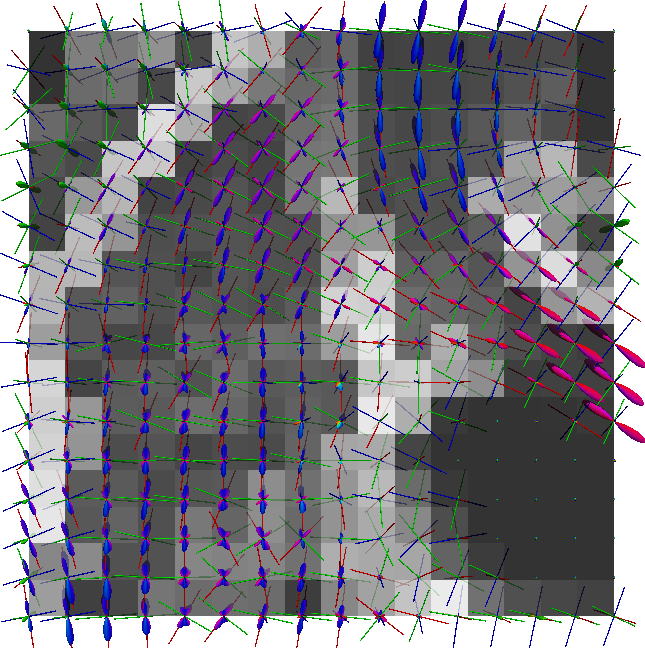

Non-negative spherical deconvolution (NNSD) (Cheng et al., 2014) is performed to estimate non-negative fiber ODFs from three-shell DWI data. NNSD works for multi-shell data. It is more robust to noise, and the obtained fiber ODFs (fODFs) in isotropic regions are closer to the isotropic spherical PDF, compared with conventional constrained spherical deconvolution (Tournier et al., 2007). After obtaining the fODFs by NNSD, the peaks are detected from the estimated fODFs with GFA larger than , as described in Section 3.4. OO and OD are calculated from the spherical harmonic representation of fODFs along their principal peaks as shown in Algorithm 1. The second row in Fig. 11 demonstrates FA from tensors estimated by DTI, OO and OD from fODFs estimated by NNSD, and the total distortion map estimated from the local orthogonal frames of fODFs. Fig. 12 and 13 show the close-up views of fODFs, local orthogonal frames, and the six proposed indices for the red and blue regions in Fig. 11, where the region shown in 12 is also visualized in the DFA pipeline in Fig. 1. The fODF glyphs are colored by using its sampled directions. The three orientations in the local orthogonal frame in each voxel are visualized by using three tubes in red, green, and blue colors respectively. There is no local orthogonal frame in some voxels because those voxels have GFA values lower than . These figures show the following: 1) OO is high in anisotropic areas with well-aligned directions, while OD is high in isotropic or crossing areas. 2) The four orientational distortion indices are low in areas with well aligned principal directions, and zero in isotropic voxels without peaks. Distortion indices are high in voxels where the principal directions in its local neighborhood change largely. 3) The central voxels in red region is the crossing area of the Corpus Callosum from left to right and Fornix that goes through the coronal slice. The twist index showed high value in this crossing area as expected.